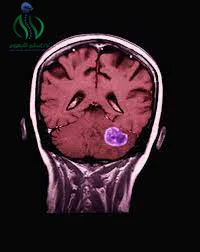

- يمكن أن يتم استخدام الأشعة السينية، والتصوير بالرنين المغناطيسي (MRI)، والتصوير بالموجات فوق الصوت (الألتراسونوجرافيا) للحصول على صور دقيقة للورم وتحديد حجمه ومكانه.